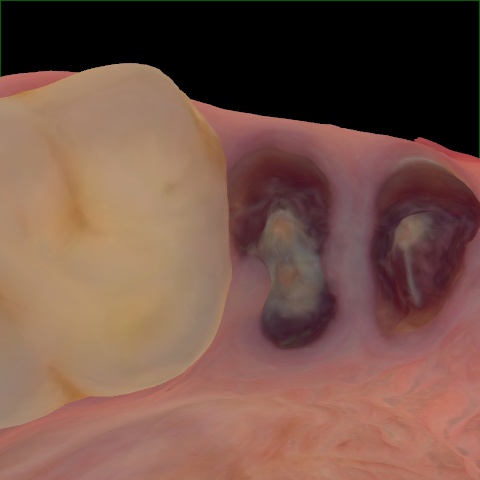

Incorrect Quality Level

The reference annotation for this image is

None

.

Please select the correct quality level.

Annotated as "Good"